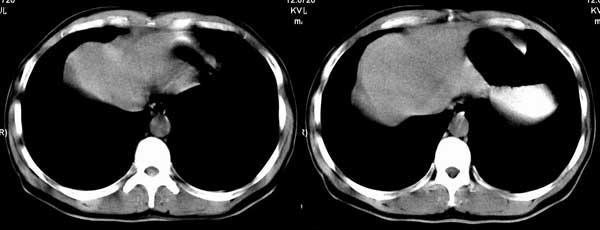

以下是引用听蝉观竹在2005-2-15 23:30:28的发言:[br]胃窦癌。[br]建议做胃镜检查并活检。